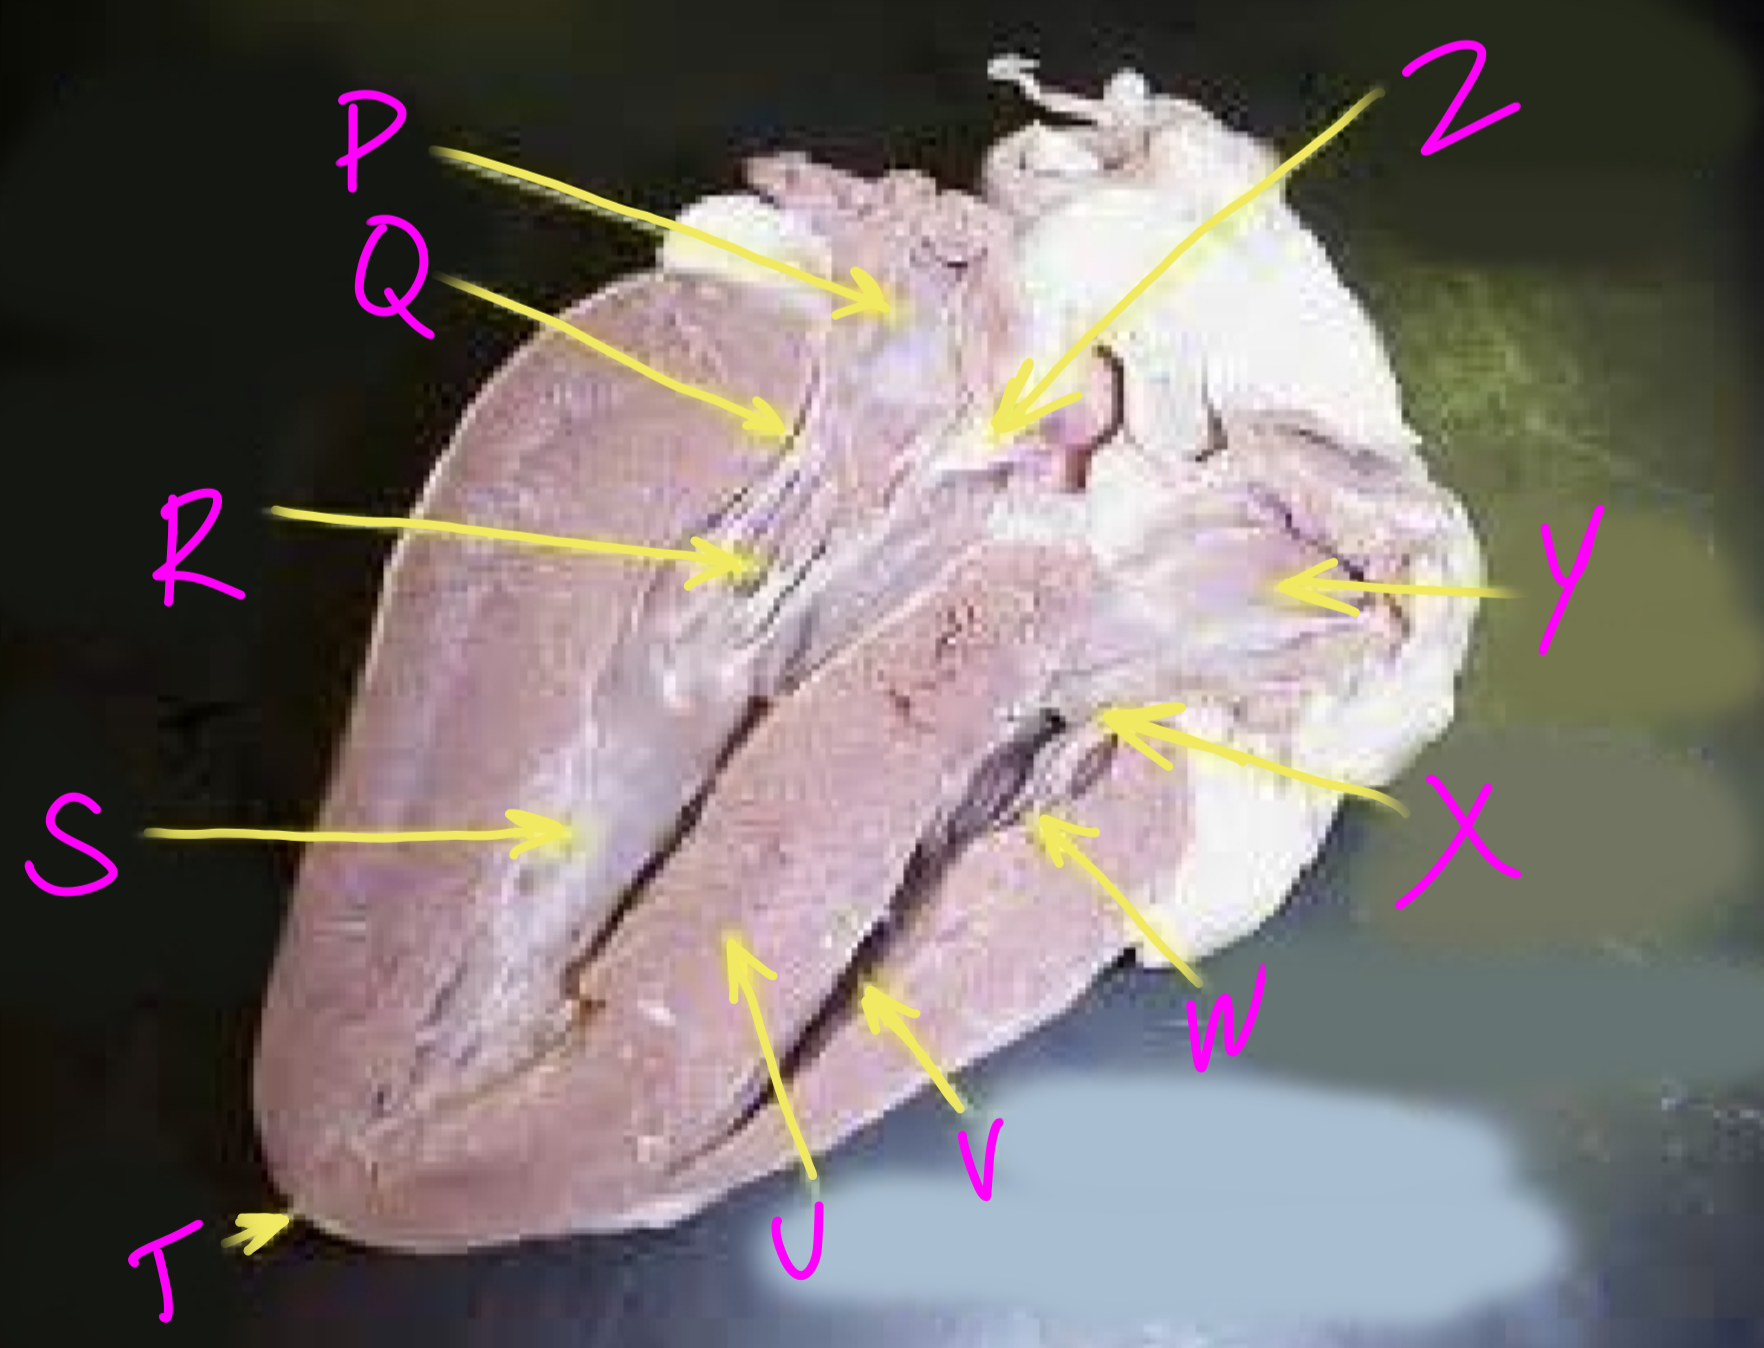

P

Left atrium

Q

Bicuspid valve - allows blood to flow from the left ventricle to the aorta

R

Right chordae tendinae - hold AV valves in place

S

Left ventricle

T

Apex - pumps blood out of the ventricles

U

Interventricular septum - divides the right and left ventricles

V

Right ventricle

W

Left chordae tendinae - hold AV valves in place

X

Tricuspid valve

Y

Right atrium

Z

Aortic semilunar valve - prevent backflow